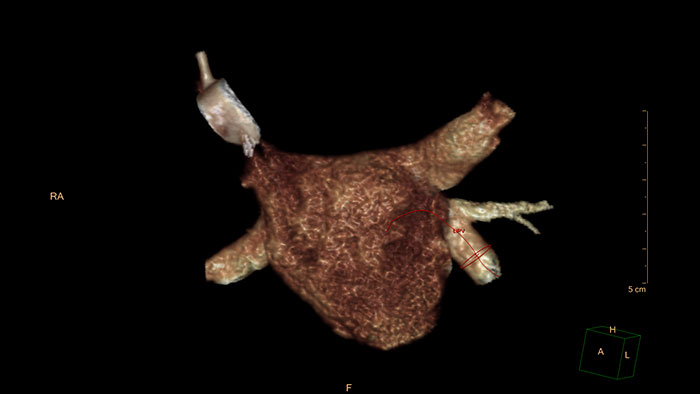

Obrazowanie CT na potrzeby planowania TAVI w zaawansowanej diagnostyce pacjenta

Dostęp do funkcji półautomatycznych pomiarów aorty i zastawki aortalnej przydatnych na etapie planowania zabiegu TAVI.

Uproszczony proces tworzenia modeli, zoptymalizowany pod kątem wydruku na drukarkach 3D

System IntelliSpace Portal zawiera dedykowaną aplikację 3D Modeling przeznaczoną do tworzenia i eksportowania trójwymiarowych modeli. To zintegrowane środowisko programowe zapewnia dostęp do narzędzi segmentacji systemu IntelliSpace Portal zebranych w jednym miejscu w celu uproszczenia przebiegu pracy.

– Aplikacja 3D Modeling umożliwia łatwy eksport plików zestawów danych w standardowych formatach (takich jak STL) oraz w formacie 3D PDF, który można wykorzystać do wymiany informacji w obrębie placówki. – Dostępność różnych opcji eksportu usprawnia przesyłanie plików do usługi drukowania, jak również w obrębie szpitala na użytek wewnętrzny.